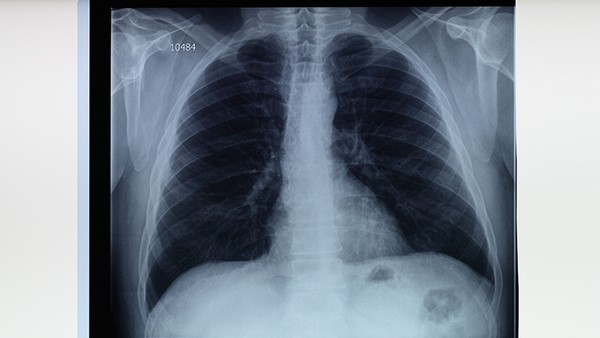

得过肺结核痊愈之后是可以献血的。但是在献完血之后需要做好自身的护理工作。